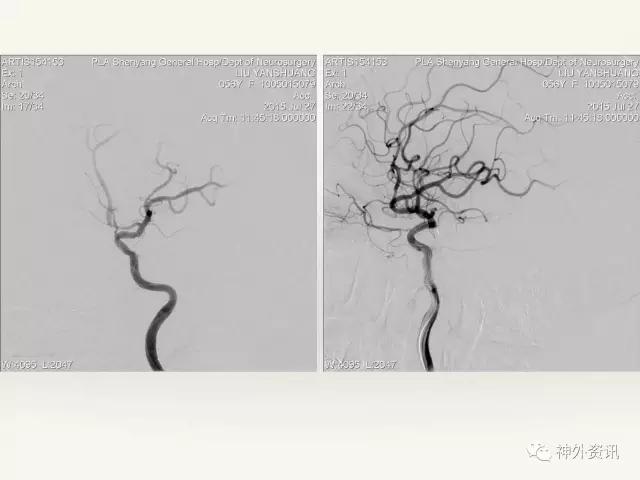

在东北地区率先开展了颈内动脉、大脑中动脉及基底动脉闭塞血管内再通、颅内动脉栓塞急性期取栓、血流导向装置治疗大型宽颈动脉瘤等,对颅内动脉瘤、动静脉畸形、颈动脉及颅内动脉狭窄、颈内动脉海绵窦瘘、硬脑膜动静脉瘘等外科治疗具有较深的造诣。完成脑血管造影8600余例,各类脑血管病介入手术共4500余例,动脉瘤、动静脉畸形、脑肿瘤、脑出血及脑外伤等外科手术1500余例。